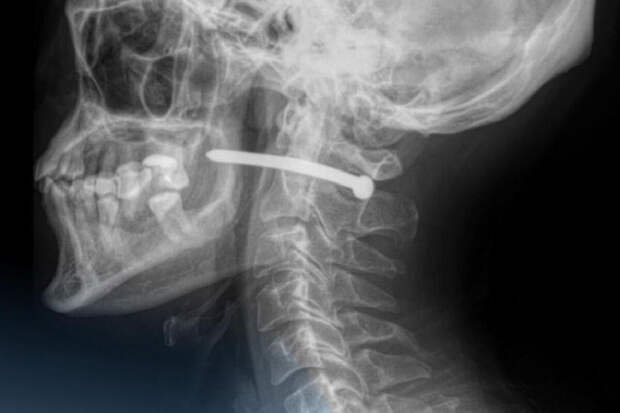

Рентген показал, что металлический предмет прошел буквально в миллиметрах от шейного отдела позвоночника. Медики отметили, что мужчине невероятно повезло — жизненно важные органы и сосуды не были повреждены.

Хирурги извлекли гвоздь, тщательно обработали рану и наложили швы. После процедуры пациента отпустили домой с рекомендациями. Врачи напомнили, что любые травмы шеи представляют серьезную опасность, ведь в этой области проходят крупные артерии, нервы, дыхательные пути и спинной мозг.